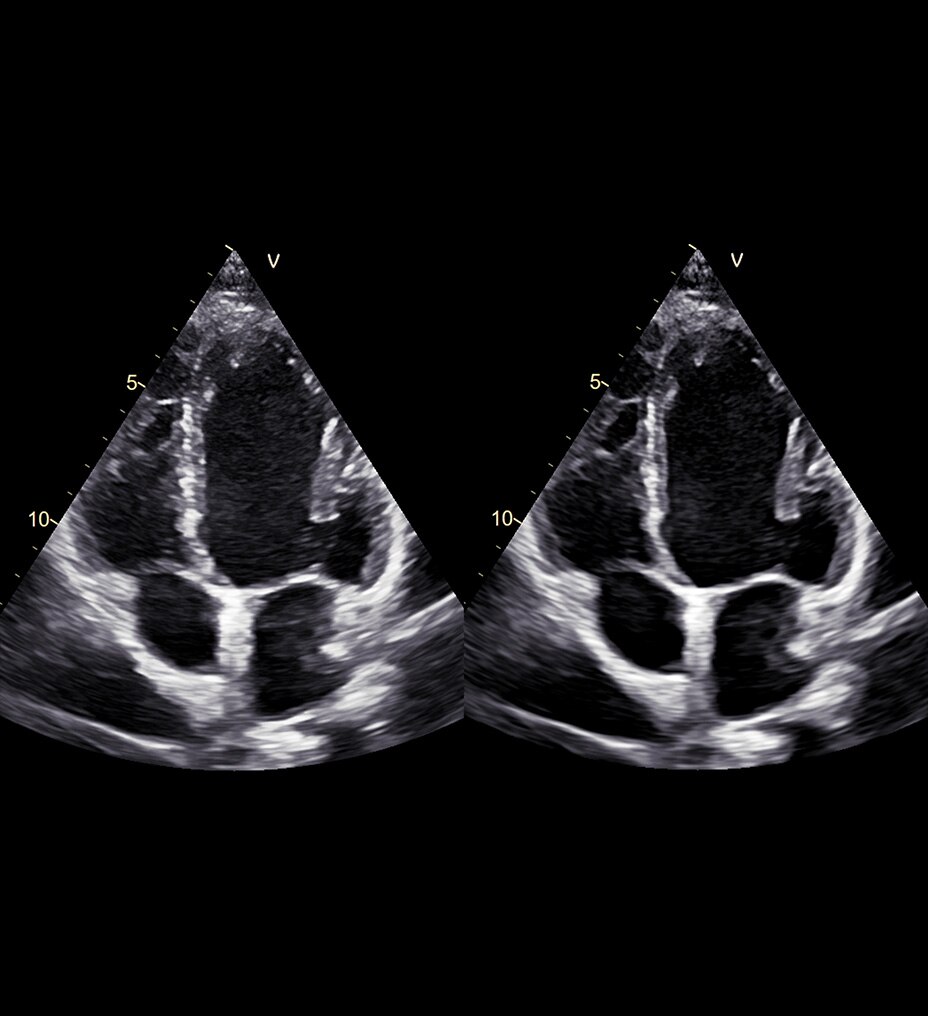

SONOLYST IR

Simply scan, then freeze

Using ISUOG practice guidelines, SonoLystIR automatically detects recommended views. It identifies anatomy, then selects applicable annotations and measurements. Confirm and data is entered into the Scan Assistant checklist and report, enhancing workflow and reducing variability.